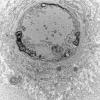

PERIPHERAL NEUROPATHY

0 PNS ARTIFACTS (6)